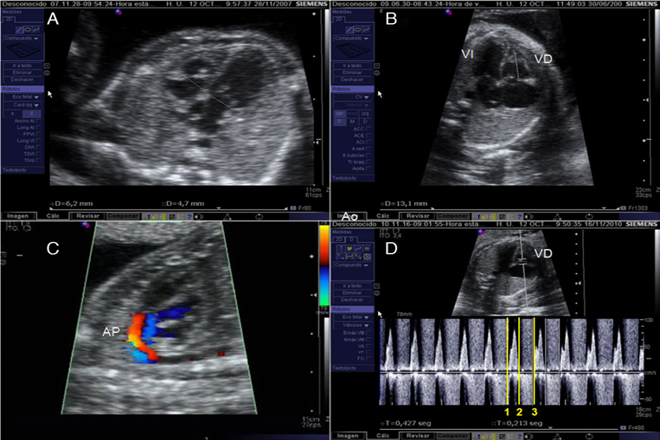

Para la evaluación cardíaca se necesita la proyección cardíaca de 4 cámaras, y se analiza el situs cardíaco. El situs es la posición que ocupa el órgano en relación a la simetría corporal del cuerpo, el primer paso es determinar la posición fetal, estableciendo el lado derecho, izquierdo, anterior, posterior, superior e inferior, luego determinar que el estómago esté del lado izquierdo, podemos determinar el situs cardíaco y visceral, el situs visceral es una condición en la cual el lóbulo mayor del hígado está sobre el lado derecho y el bazo, la aorta descendente y el estómago del lado izquierdo. Usando la posición de la vena cava inferior (derecha) y la aorta (izquierda) con respecto a la columna ayuda a establecer también el solitus.  La posición usual del corazón es anterior  y a la izquierda de la caja torácica, la punta del ápex normalmente entre 45+/- 20 grados, el tamaño del corazón ocupa normalmente un tercio de la caja torácica, el retorno de las venas pulmonares ocurre en el atrio izquierdo visualizado con el doppler color, la observación de la aurícula implica valorar el septum interatrial, en el lado izquierdo puede ser visible el drenaje venoso pulmonar y la lámina del foramen oval, en la aurícula derecha se observa el drenaje de la vena cava, la lamina del foramen oval debe verse con buena movilidad en la aurícula izquierda. Las valvas atrioventriculares. La tricúspide se localiza ligeramente más apical que la válvula mitral. El ventrículo derecho se identifica por la banda moderadora, debe valorarse el tamaño proporcional de los ventrículos y el septum interventricular.

En el mismo plano, el Ultrasonografista, debe mover ligeramente el transductor de la porción caudal a la porción craneal del feto, con este ligero movimiento podemos observar el tracto de salida del corazón y la posición de los tres vasos con respecto a la traquea. Se observa la aorta más posterior a la pulmonar y el cruzamiento de ambos vasos.